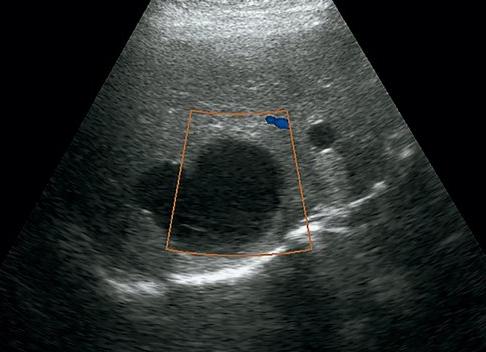

Иногда в УЗИ-заключениях в яичнике – левом или правом врач пишет о наличии анэхогенных образований. Эхогенность – это термин, применяемый в ультразвуковой диагностике для обозначения проводимости тканями ультразвуковых волн. Такие ткани, как кость, полностью отражают ультразвук из-за своей высокой плотности, также он полностью отражается на границе органов и тканей, которые содержат воздух. Плотные ткани сильнее отражают ультразвук, а те, в которых содержится много жидкости, проводят сигнал ультразвукового датчика, усиливая его при этом.